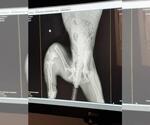

Dog Breed: Doberman Pinscher / Mixed. Trinity - A Doberman X puppy- A Survivor Soon Ready for Her Forever Home Meet Trinity, a 5-month-old Doberman mix who, despite her tough beginnings, is full of spirit, resilience, and love. Found days later in the same area as her likely sibling, Quinn, Trinity has had a difficult start. Not only did she suffer a severely broken leg, but her emaciated little body was also covered in bite wounds—likely from other animals. These injuries are a testament to the harsh reality she faced on her own before being rescued. X-rays revealed that her leg was broken in four places, and the bones are severely infected. Sadly the vet feels, the injury is beyond repair, and after careful consideration, her leg will be amputated to help her heal. Trinity is no stranger to overcoming obstacles. Even through her pain and uncertainty, she remains a sweet and affectionate pup, eager to bond with those around her. Adopting Trinity: A Rewarding Journey Once Trinity has fully recovered from her surgery and rehabilitation, she will be ready to begin a new chapter of her life with a family who will provide the love and care she deserves. Trinity is a survivor, and she is sure to make a loyal, loving companion. While she may be missing one leg, her heart is as big as ever, and she’s expected to adapt quickly to her new way of life—still full of playful energy and the affectionate nature that makes her such a special pup. If you are looking for a brave, loving, and resilient pup to welcome into your home, Trinity could be the perfect fit for you. She will need an environment that can support her during her recovery but also a place where she can live out her life as an active and joyful member of the family. Trinity’s playful personality and loving nature will be the perfect addition to the right home, and she’s sure to return the love tenfold. This girl is everyone's friend! What Trinity Needs in Her Forever Home: A patient and understanding family ready to support her through her recovery and beyond. A home with a secure yard where she can play safely and get the exercise she needs. A calm and loving environment where she can heal physically and emotionally. A family willing to continue her training and make sure she gets the care she needs for her leg amputation. How You Can Help: We are still seeking donations to cover Trinity’s medical expenses, including her surgery and rehabilitation. Your support will help her recover and thrive as she prepares for adoption. Once she’s fully healed, Trinity will be ready to give her new family all the love and companionship they could ever need. If you are interested in adopting Trinity or would like to learn more about how you can help, please reach out to us. She’s a survivor, and with your help, she can have the life she was always meant to live—full of love, care, and happiness. A Reminder: Trinity’s story is a heartbreaking yet inspiring reminder of why it’s so important to spay and neuter pets. It’s also a powerful example of how every little bit of love and support can change the life of an animal in need. Will you be the one to offer Trinity her second chance? She’s waiting for her forever home—and that home could be with you. .uniteddobermanrescue United Doberman Rescue Adoption Process Application Submission: Complete the adoption application thoroughly. Incomplete applications may be denied.(uniteddobermanrescue) We are 100% volunteer, please read adoption requirements BEFORE reaching out to us. Home Visit: A volunteer will schedule a home visit to assess the environment and discuss your expectations. All household members, including children, must be present.(uniteddobermanrescue) Veterinary Reference Check: Provide contact information for your current veterinarian. All existing pets must be spayed/neutered, current on vaccinations, and on heartworm preventative.(uniteddobermanrescue) Meeting Dogs: Once approved, you'll have the opportunity to meet adoptable dogs in their foster homes. If you have a resident dog, consult with the foster about bringing them along. Adoption Finalization: If a suitable match is found, you'll sign an adoption contract and pay the adoption fee. Due to COVID-19 precautions, same-day adoptions are currently permitted. Key Adoption Policies Age Requirement: Adopters must be at least 21 years old and reside in the home where the dog will live.(uniteddobermanrescue) WE do NOT ship our dogs ever!!! Children: Adult dogs are not placed in homes with children under 6 years old. Puppies may be considered for such homes if a fenced yard is present.(uniteddobermanrescue) Living Arrangements: Dogs must live indoors and not be left unattended outdoors. Training Commitment: Adopters should be prepared to continue training and socialization. Formal obedience classes are encouraged.(uniteddobermanrescue) Health Considerations: Dobermans are prone to certain health issues. Adopters should be financially prepared for potential veterinary expenses and consider pet insurance. Return Policy: If you're unable to keep your adopted dog, UDR requires the dog be returned to them, except in cases involving aggression or biting.(uniteddobermanrescue) {s8319code4181/} We follow the Doberman Pinscher Club of America's Code of Ethics. For more information visit the DPCA at .dpca